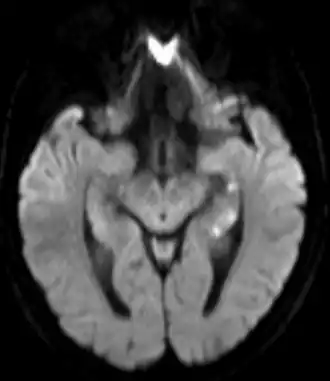

L'examen neurologique est normal pendant et après la crise ainsi que l'imagerie cérébrale[7]. Il peut exister cependant des images punctiformes au niveau de l'hippocampe à l'IRM cérébrale, mais qui sont retardées et transitoires[10], ce qui explique que l'on passe souvent à côté. Le déficit dure, en moyenne, six heures[7].